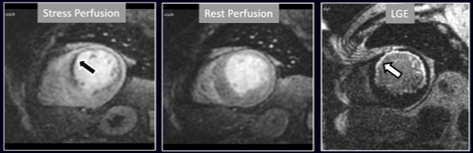

The most immediate and commonest method of analysis is the visual detection of a distinctive deficient increase in signal intensity of a region of the left ventricular myocardium during the first passage of a CA bolus under vasodilatory conditions lasting for at least 3 consecutive frames of the sequence. This perfusion defect should not be present at rest and should not correspond to an area of previous MI. The detection of such a defect is assumed to be due to a reduction in CFR of this territory which, when attributed to a particular coronary artery [39], allows for the conclusion of the presence of a significant epicardial stenosis in the vessel (Fig. 6).

Fig. 6.Single-vessel perfusion defect. Extensive subendocardial perfusion defect at the antero-septal region (arrow, on the upper left panel) not present at rest, in a region without LGE (lower left panel). Angiography proves this defect to be due to a tight stenosis of the LAD coronary artery (arrow, on the lower right panel).

The presence of inducible residual peri-infarction ischemia in a territory with a previous MI has been addressed by the consideration of the extension of a stress perfusion defect in comparison with that of the LGE. Those defects with equal size on both sequences would be labelled as “fixed” (Fig. 16), while those perfusion defects exceeding the area of MI would be considered as “partially reversible” (Fig. 17), independently of rest perfusion studies. The diagnostic performance of the latter finding for the diagnosis of a residual significant stenosis in the infarct-related artery has been found to be adequate, though a good deal of cases with apparently fixed defects had also significantly obstructed arteries [46].

Fig. 16.Stress/Rest perfusion in chronic myocardial infarction. Perfusion defect during stress (performed in first place) (black arrow), not present at rest, matching the area of LGE (white arrow) in a case of large anterior subendocardial MI.

Fig. 17.Stress/Rest perfusion in chronic myocardial infarction. Perfusion defect during stress (performed in first place) (white arrow), not present at rest, fairly larger than the region of LGE (black arrow) in a patient with a subendocardial inferior MI.